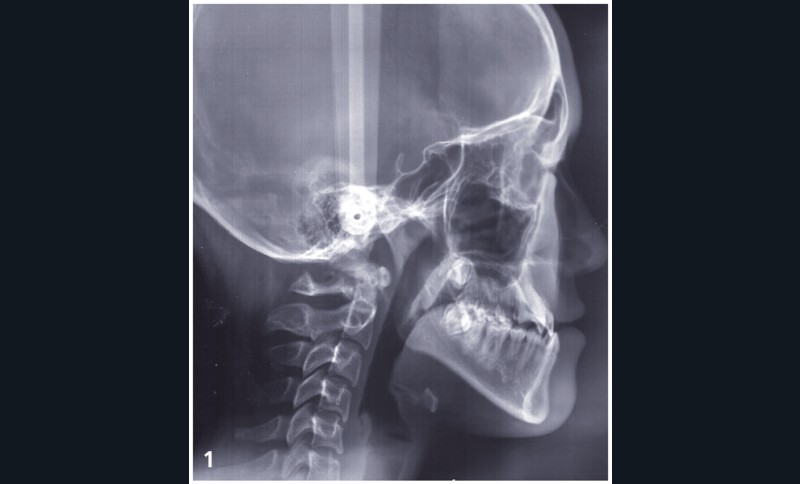

Diagnostic (fig. 1 à 3)

Sylvie se présente à l’âge de 15 ans avec une classe III squelettique (ANB -7,6°) d’origine maxillaire et mandibulaire sur un schéma facial à tendance hyperdivergent (FMA 31°) (fig. 1).